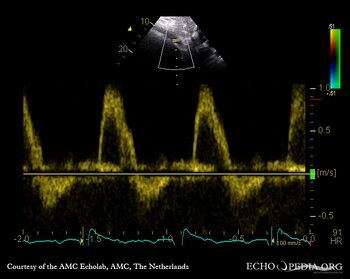

A4CH: Color Doppler, severe aortic regurgitation Continuous-wave doppler signal of severe aortic regurgitation

Pulsed-wave signal of flow in abdominal aorta, diastolic flow reversal